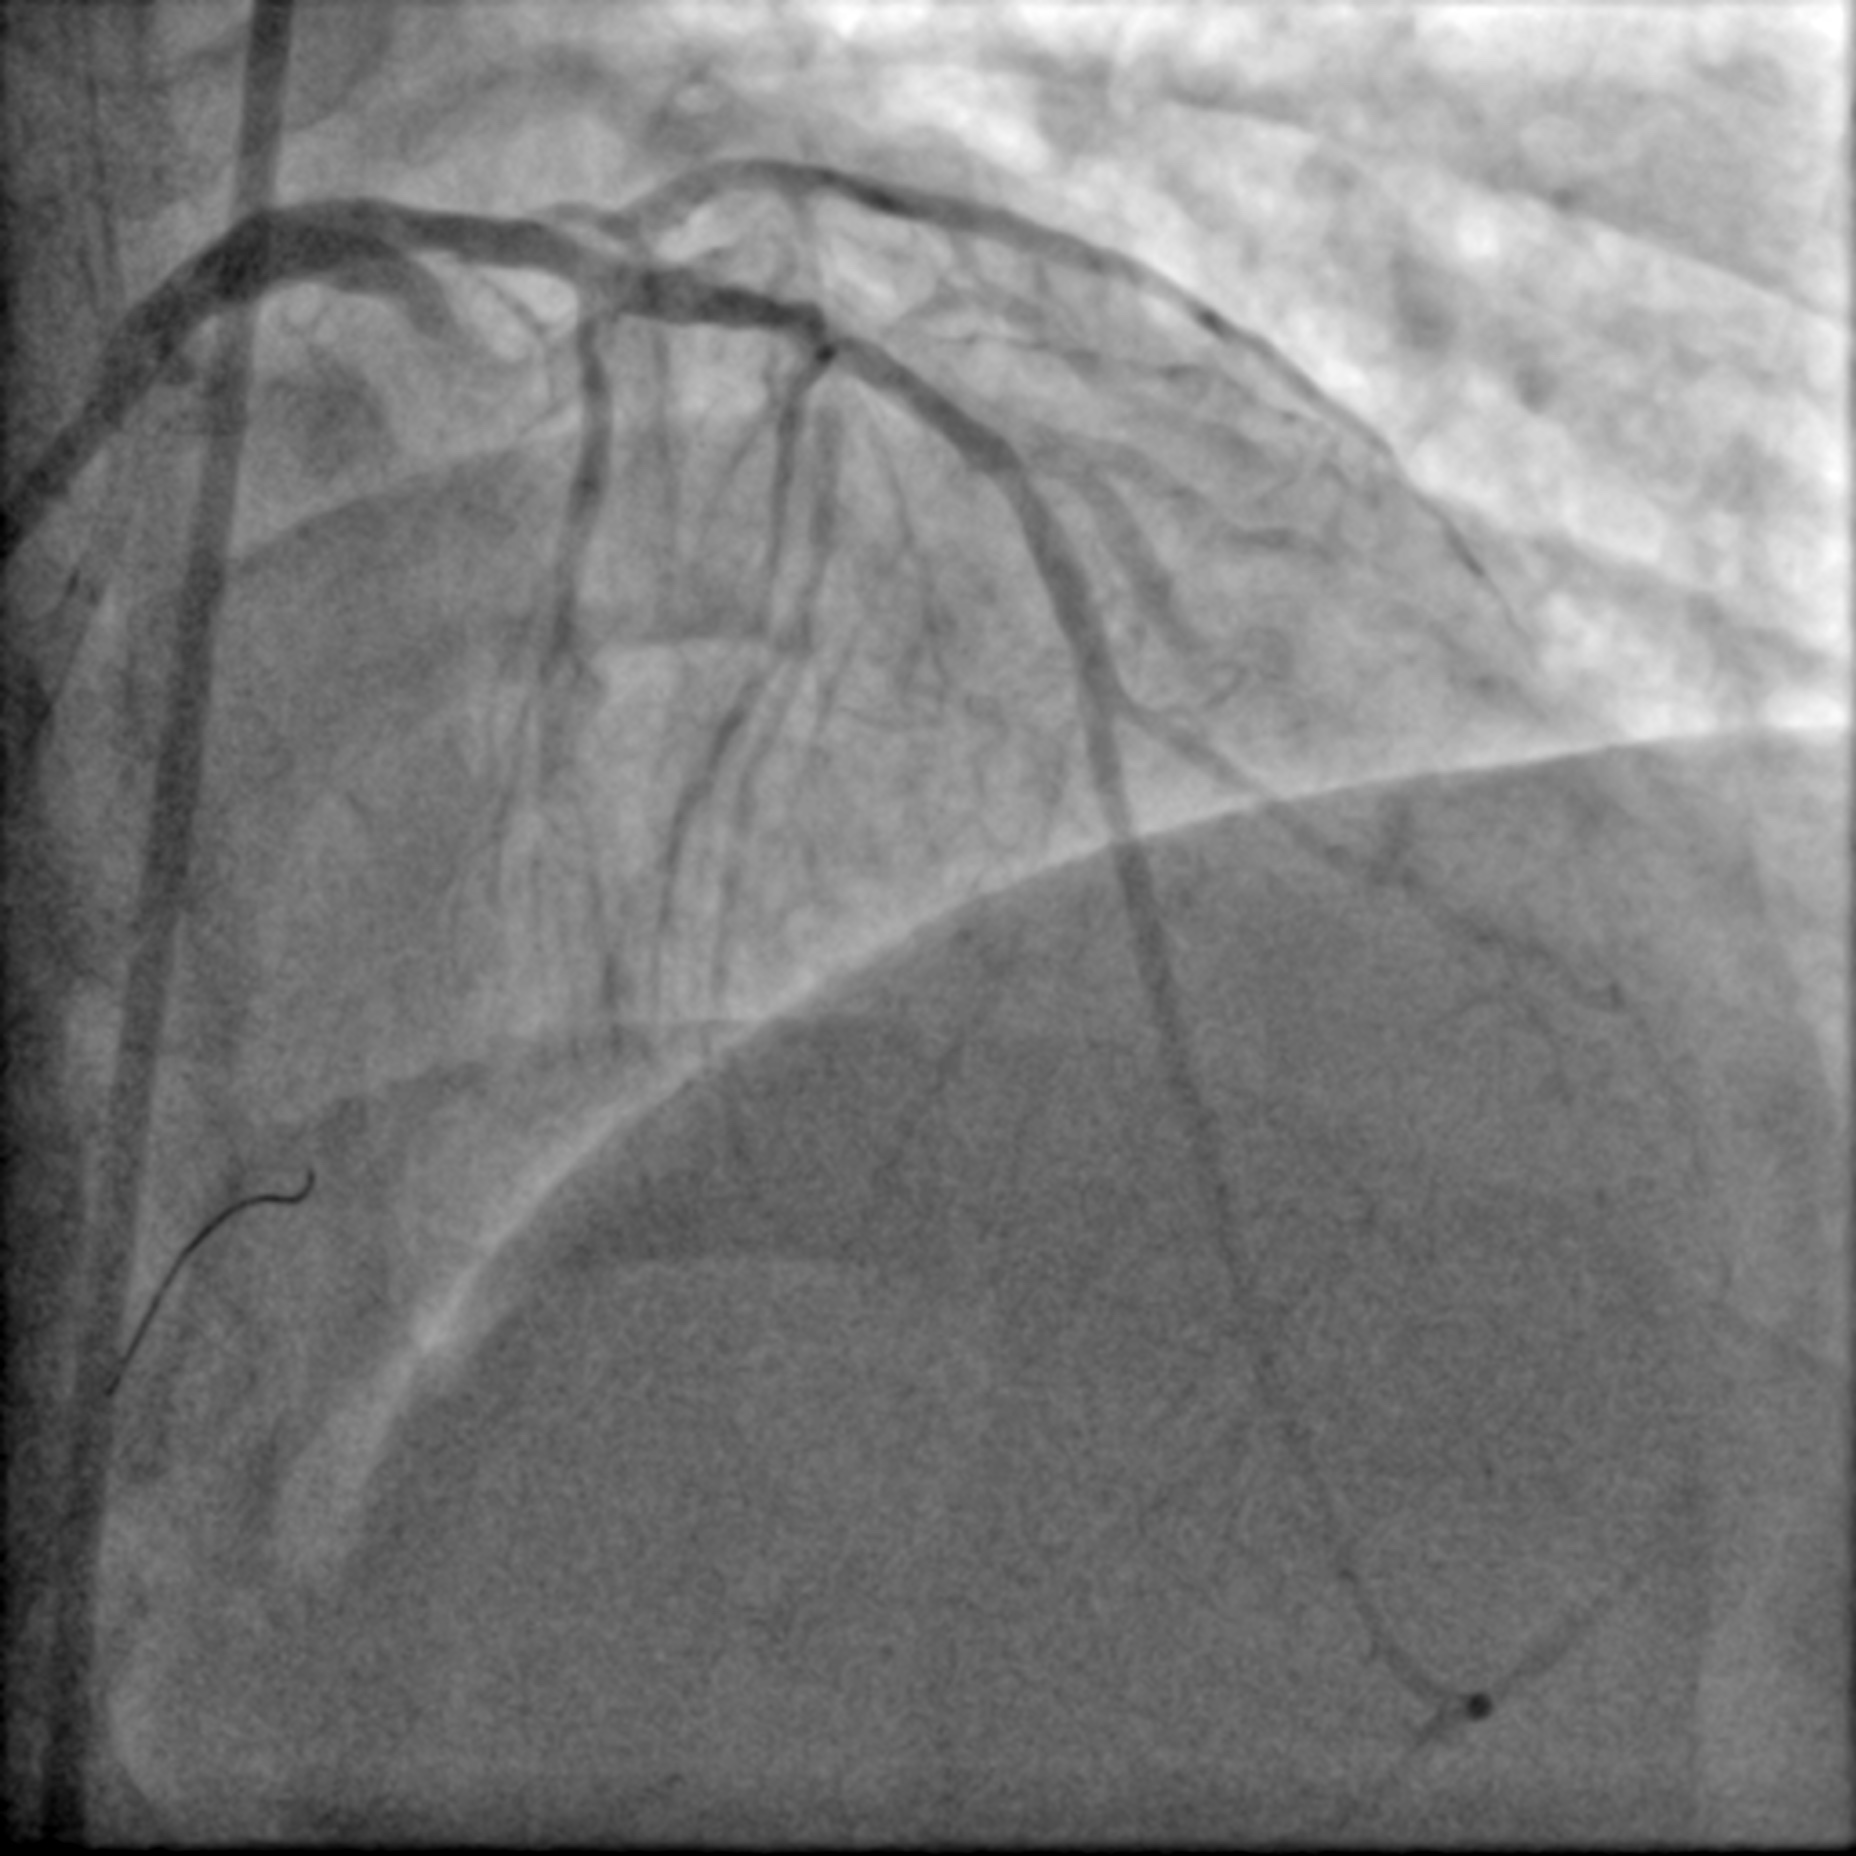

The proximal LAD demonstrates a Chronic Total Occlusion (CTO) with collateral flow from the Right Coronary Artery (RCA) via a septal perforator. The J-CTO score is 2, attributed to a blunt proximal cap and an estimated lesion length of more than 20 mm. The indication for CTO intervention is angina refractory to medical therapy. The procedure was planned using an antegrade approach via a 7 Fr EBU 3.5 catheter, with a contralateral injection from the RCA for visualisation.

With the support of a FineCross micro-catheter (MC), the proximal CTO cap was punctured with a Gaia First wire. The wire traversed the CTO body through the intra-plaque space without much difficulty, reaching the distal lumen, which was confirmed by contralateral injection. However, the MC could not be delivered to the distal lumen over the Gaia First wire. The CTO lesion was pre-dilated with a 1.0 mm balloon, but it burst during the fourth inflation, and the MC still failed to advance. Subsequently, a trapped foreign body was noted on the distal aspect of the wire that prevented the advancement of the MC. This was initially thought to be a fragment fractured from the 1.0 mm balloon. The intervention was continued over the Gaia First wire to facilitate the removal of the fragment. The lesion was pre-dilated with a 2.5 mm non-compliant (NC) balloon and a 3.5 mm cutting balloon. Two 3.5 mm drug-coated balloons (DCBs) were then used to treat the lesion. With adequate luminal gain, an extension catheter was advanced into the LAD, and the fragment was retrieved inside it. A 1.5 mm balloon was then deployed to trap the fragment inside the extension catheter. The wire, extension catheter, and inflated 1.5 mm balloon were then removed simultaneously from the LAD. Inspection of the wire revealed that the fragment was, in fact, an unraveled coronary wire rather than a fractured balloon.